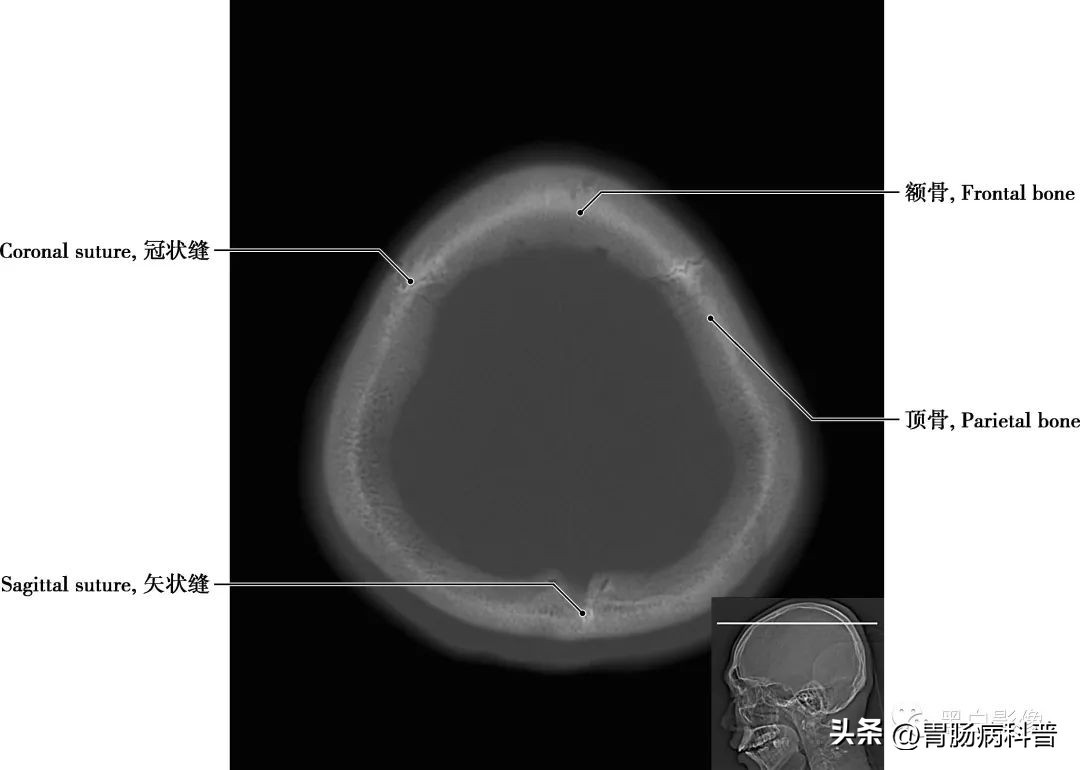

图1-2-4 经中央旁小叶下部轴位切面

冠状缝 顶骨与额骨之间的骨缝,呈冠状位走行

图1-2-5 经半卵圆中心轴位切面

矢状缝 两顶骨之间所成的缝隙,呈矢状位走行